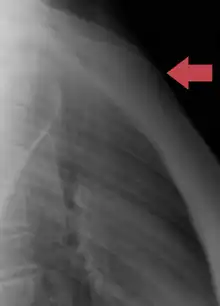

Sternum cut along the frontal plane showing interior of the bone Sternum, lateral aspect

Sternum, lateral aspect Position of the sternum the thoracic cage